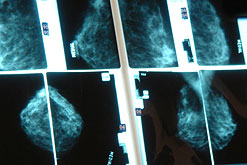

Are MRI scans better at detecting an early form of breast cancer than standard mammograms?

Recent research has suggested that MRI scans are far better at detecting an early form of breast cancer than standard mammograms. The study - published in The Lancet - focused on an early form of breast cancer called DCIS. Jane is joined by Dr Emma Pennery of Breast Cancer Care to discuss these latest findings and their implications regarding screening for breast cancer.